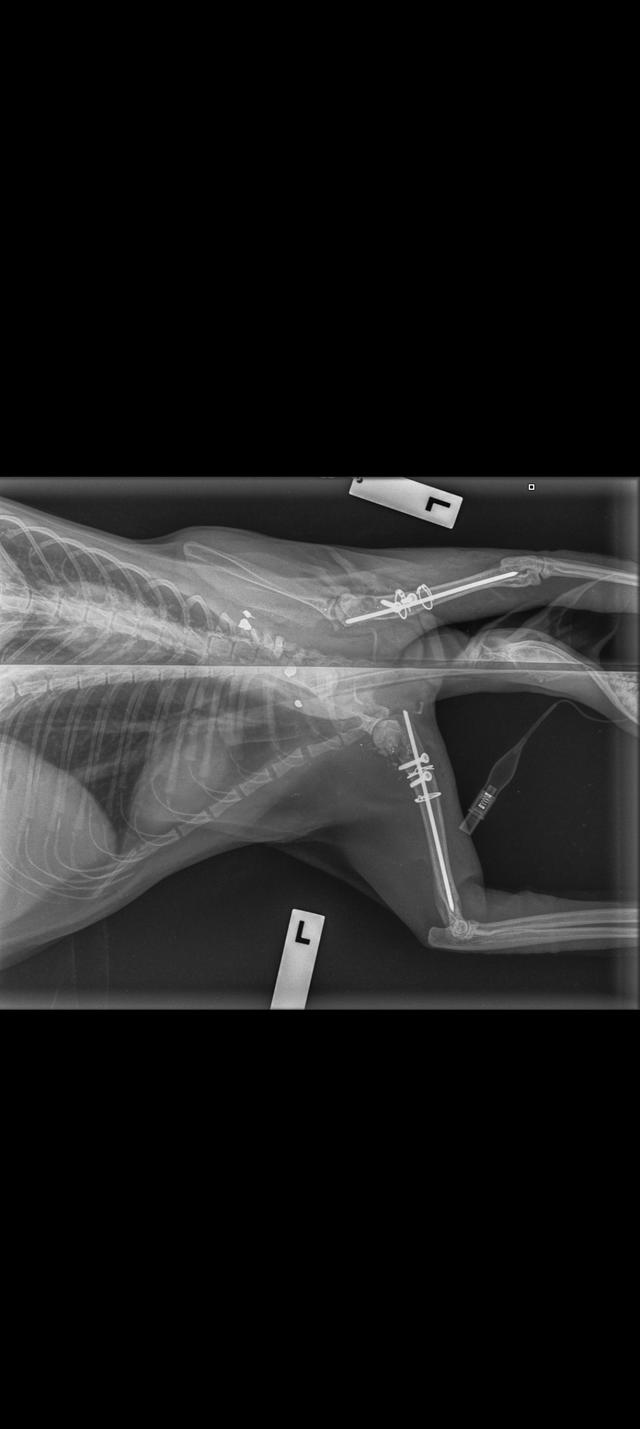

Main image

Thought I would update everyone on how Abby is doing. She's only got a couple more weeks left in her crate then she's allowed out to carry on being Abby.

You wouldn't think she was shot, she's naughty as and has gotten out of her crate every chance she's found, just lucky she hasn't been able to get out of the room she's been in.

I have add photos of her x-rays that were done on the 18/1/22.